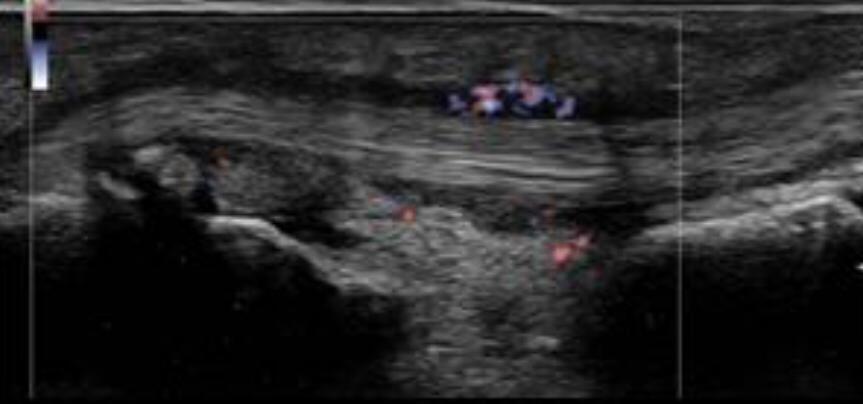

Trigger finger is a type of stenosing tenosynovitis. It develops due to repetitive microinjury from frequent flexion-extension movements of the fingers.

Primary trigger finger occurs most commonly in the middle fifth to sixth decades of life and up to 6 times more frequently in women than men.

A patient with trigger finger finds it difficult to straighten or bend the affected finger. The finger transiently gets locked in the flexed position and with a painful snapping sensation goes into extension.

Thickening and hyper-vascularization of the A1 pulley are the hallmarks of trigger fingers on sonography. Other frequently observed features include distal flexor tendinosis and tenosynovitis.

The first annular pulley (A1) at the metacarpal head is by far the most often affected pulley in trigger finger, though cases of triggering have been reported at the second and third annular pulleys (A2 and A3, respectively), as well as the palmar aponeurosis.

The level of thickening can be variable with some authors suggesting the normal value being around 0.5 mm with thickening suggested when the diameter is over 1.1 mm.

The condition can be conservatively managed with splinting, NSAIDs, and local steroid injections or may require a surgical section of the A1 pulley when the pulley is markedly thickened.